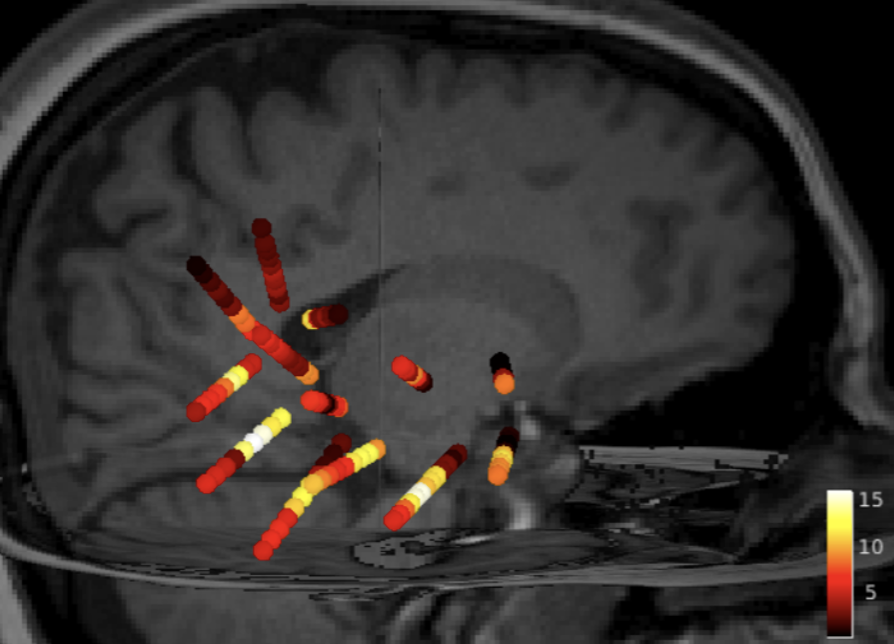

esi